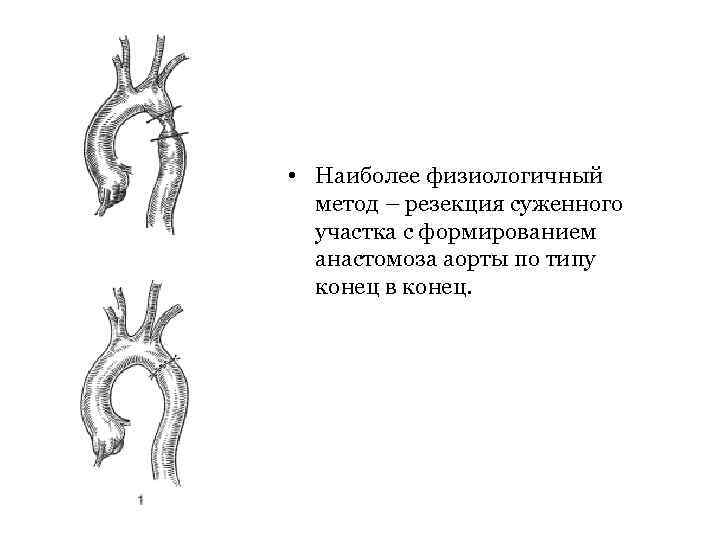

• Наиболее физиологичный метод – резекция суженного участка с формированием анастомоза аорты по типу конец в конец.

• Наиболее физиологичный метод – резекция суженного участка с формированием анастомоза аорты по типу конец в конец.

• При сужении аорты на большом протяжении и наличии аневризм приходится прибегать к протезированию аорты синтетическими трансплантатами.

• При сужении аорты на большом протяжении и наличии аневризм приходится прибегать к протезированию аорты синтетическими трансплантатами.